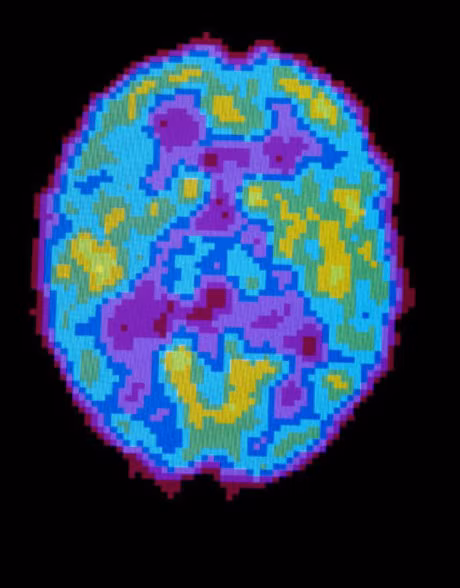

Bat ngo voi nghien cuu moi: ngu la de quen - Anh 2

Hình ảnh chụp cắt lớp bộ não khi ngủ bình thường. Hai nhà khoa học Tononi và Cirelli cho biết: Giấc ngủ có thể giúp não bộ ngăn cản sự liên kết tế bào thần kinh không cần thiết.

Ảnh: Hank Morgan/Science Source